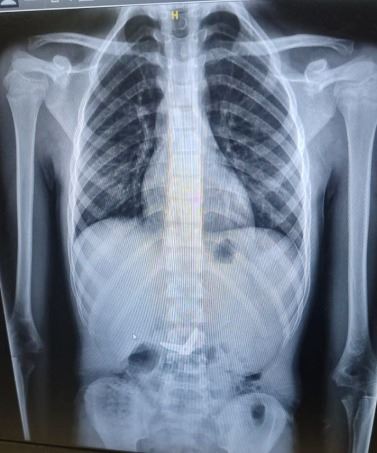

בשבוע שעבר, בשעות הלילה המאוחרות, הגיע י' יחד עם משפחתו למלר"ד ילדים במרכז הרפואי שערי צדק לאחר שבלע להבי מספריים באורך של שלושה ס"מ. לאחר צילום הרנגטן בו נראו המספריים כאשר הלהבים נמצאים במצב פתוח בקיבה, הוזעקו צוותים רפואיים בתחומי כירורגיית וגסטרו ילדים, לרבות מומחה לפרוצדורות אנדוסקופיות בילדים בשערי צדק, ד"ר אורן לדר, והוחלט להכניס את י' לחדר הניתוח באופן דחוף כדי להוציא את המספרים.

כשי' נמצא בהרדמה מלאה בחדר הניתוח, בוצע צילום נוסף כדי לבחון את מיקום ומצב המספרים. בצילום התברר כי המספריים נסגרו מעצמם, עברו את הקיבה והגיעו לעומק המעי הדק. "הייתה סכנה שהמספריים הפתוחים יגרמו לפציעה לושט או לקיבה ורצינו לבצע בדיקה על מנת לאתר ולשלוף אותם", אומרת ד"ר אסתר אורלינסקי-מאייר, מומחית בגסטרואנטרולוגיה ילדים בשערי צדק. "באורח פלא ומסיבה לא ברורה, ראינו שהמספריים נסגרו מעצמם, כך שהסכנה לפציעה בדרכי העיכול פחתה".

בתמונות:

צילום המספריים במצב פתוח בקיבה ובמצב סגור במעי הדק.